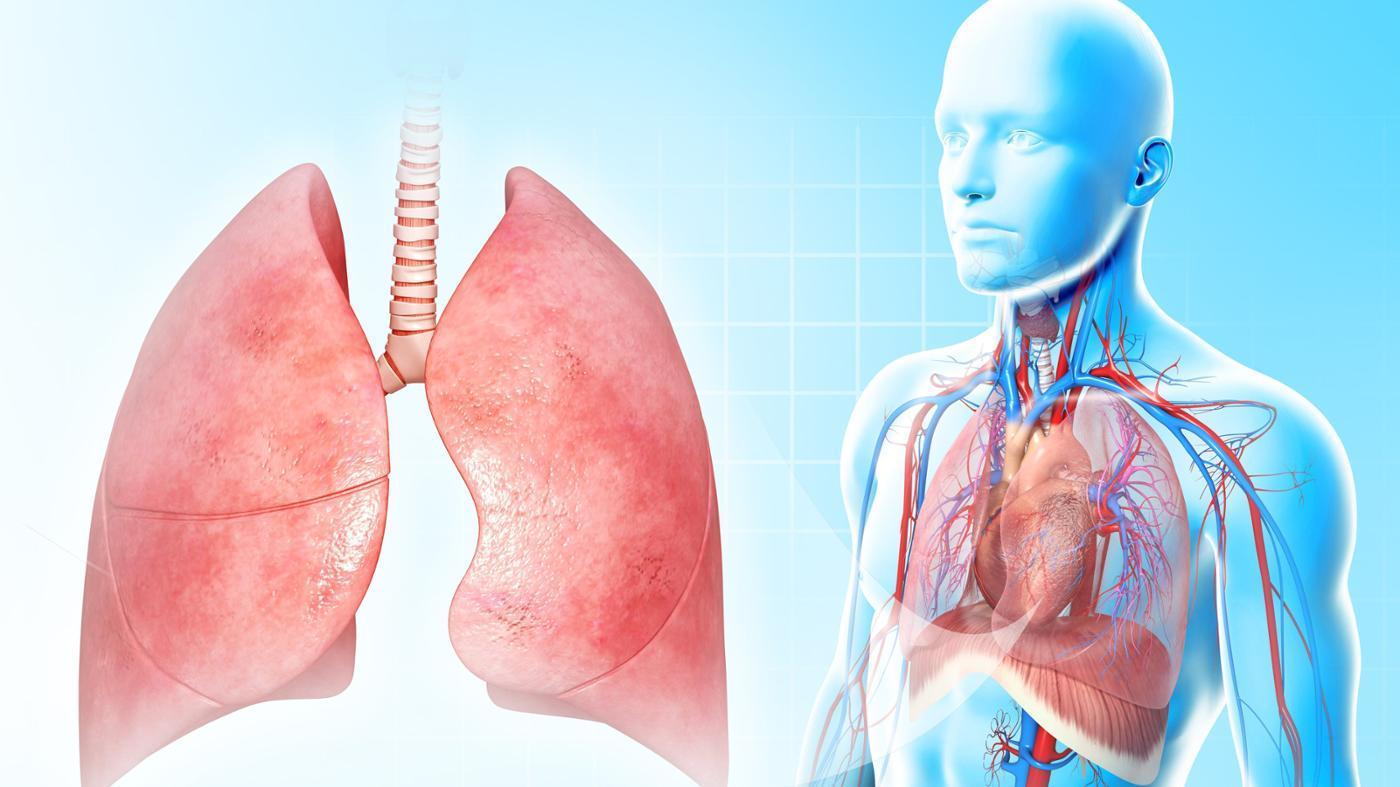

Легкие

Здоровые легкие на белом фоне

Дыхательная система человека

Легкие

Красивые легкие человека

Красивые легкие человека